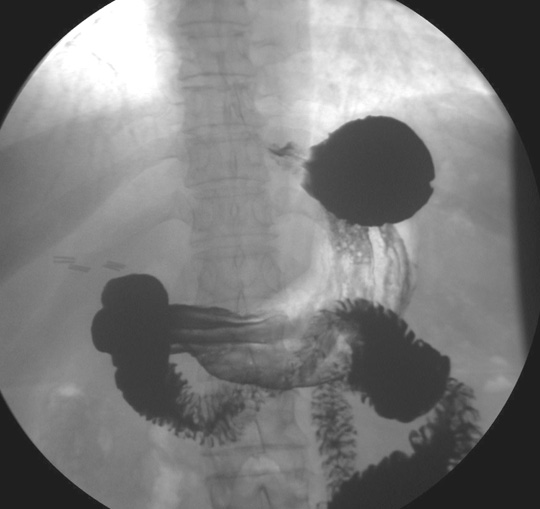

Identify the various parts of Duodenum. Click the image for labeling.